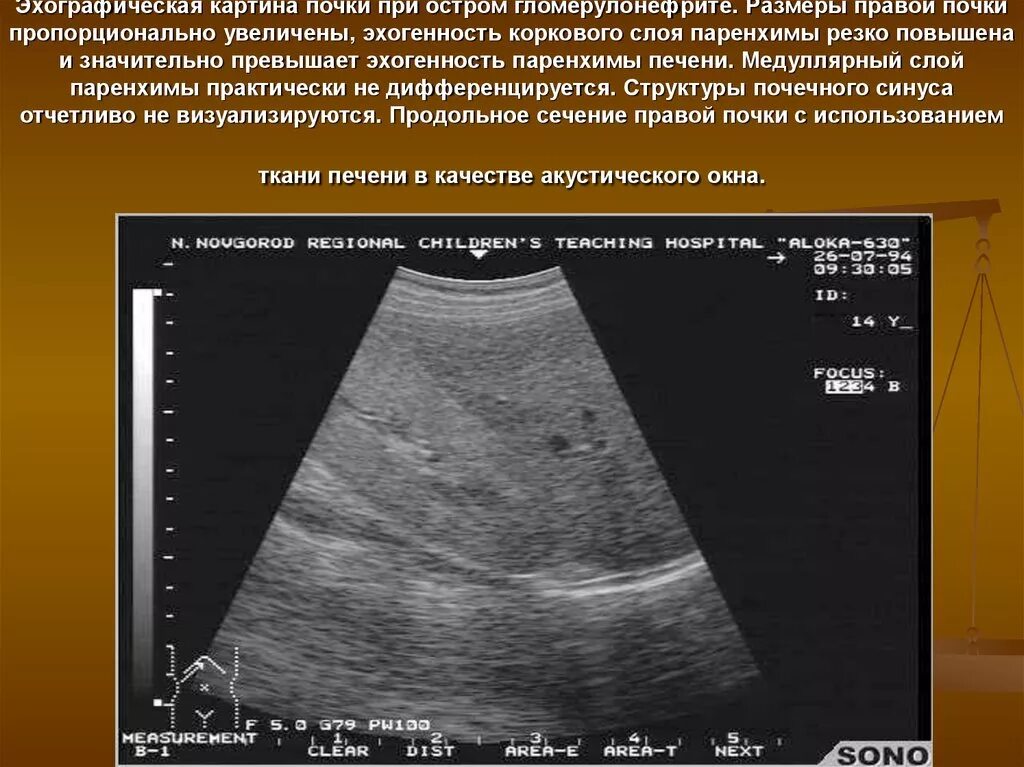

Надпочечник не визуализируется что это значит